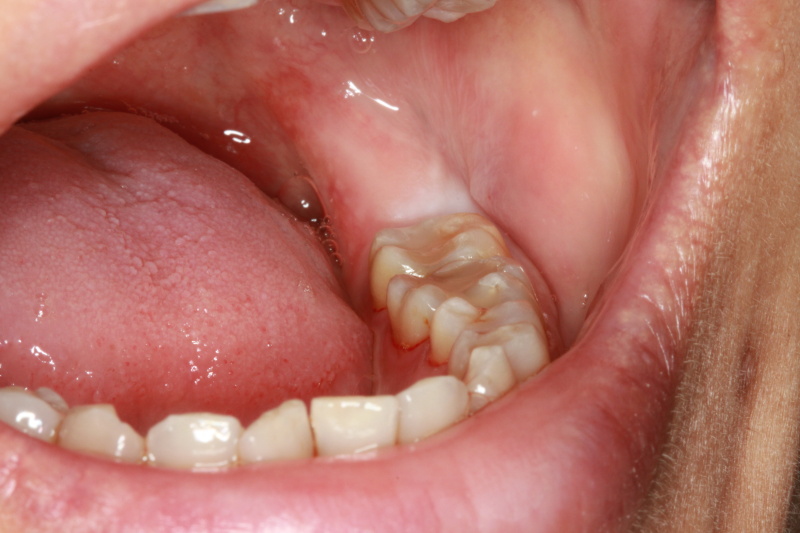

Fig 2 : Pre-operation

Fig 3 : Incision made to expose the wisdom tooth

Fig 4 : Impacted wisdom tooth exposed